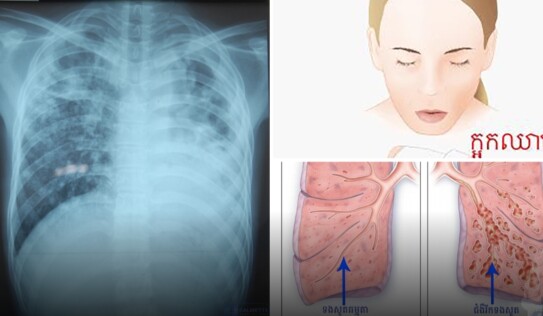

គ្រោះថ្នាក់ដល់ជីវិត! ក្អកឈាមជាសញ្ញានៃជំងឺអ្វីខ្លះ? ហើយត្រូវធ្វើយ៉ាងណាជាបន្ទាន់? 2 អាទិត្យ មុន